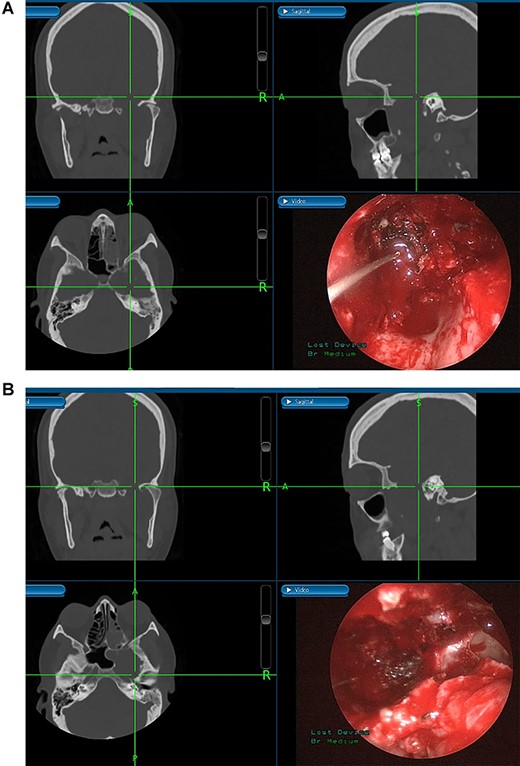

(A) Endoscopic view of the final surgical cavity after tumor removal. (B) Image-guided tumor removal from cavernous carotid artery.

The patient underwent an image-guided endonasal endoscopic tumor removal starting by endoscopic medial and posterior walls maxillectomies to control the tumor removal from the lateral sphenoid sinus and the infratemporal fossa after cauterization of the maxillary artery and sphenopalatine artery branches feeding the tumor. The tumor was dissected and removed from the cavernous (Fig. 3A) and petrous carotid artery in the middle cranial fossa (Fig. 3B). The middle cranial fossa’s dura was intact during the tumor removal (Fig. 3C). All the steps of tumor removal were controlled and monitored under image-guided navigation for accurate localization of tumor removal and avoidance of violation to the middle cranial fossa’s dura, or the brain, and the internal carotid artery in its cavernous and petrous segments (Fig. 4a and b).

Tumors in the infratemporal fossa require extensive approach such as middle fossa extraduaral approach, infratemporal fossa extradural approach, transmaxillary approach, transmandibular approach or transcervical approach. Complications from these procedures include cosmetic problems, facial nerve dysfunction, hearing loss and dental malocclusion. Image-guided endoscopic surgery allows for the preservation of intracranial structures, internal carotid artery and cranial nerves. Moreover, this procedure aids in rapid localization of the anatomical structures and meticulous intervention restricted to tumor margins. The screen is divided into four sections allowing visualization of the tumor from axial, coronal and sagittal views [10].